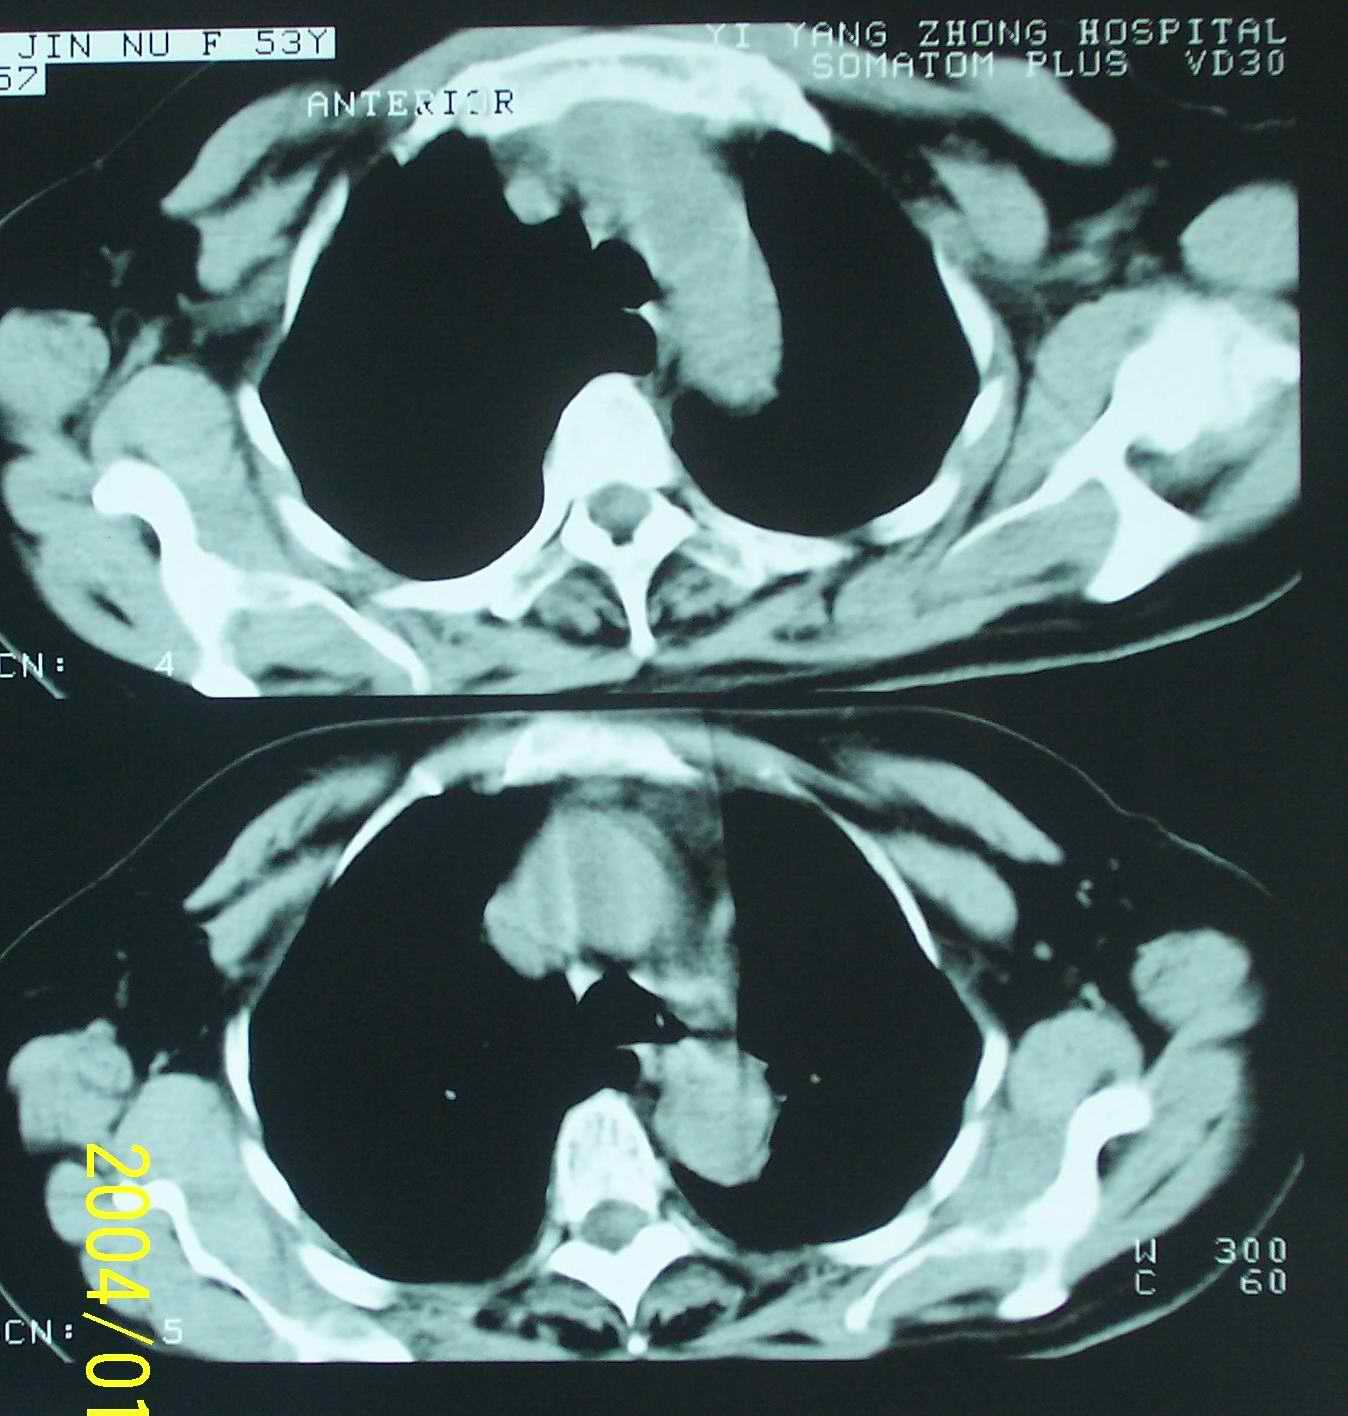

左肺下叶后基底段片状实变影,密度均匀,左肺体积缩小,膈肌上提.考虑:左下肺肺不张.

1.左侧胸腔无明显萎陷,肺体积缩小,含气量减少,纵隔心脏左移。从这个意义来讲,左下肺病灶应该首先考虑肺不张。

.左侧胸腔无明显萎陷,肺体积缩小,含气量减少,纵隔心脏左移。从这个意义来讲,左下肺病灶应该首先考虑肺不张。

补充一下病史:三天前因咳嗽咳血检查胸片见左下肺索条状影,后复查ct